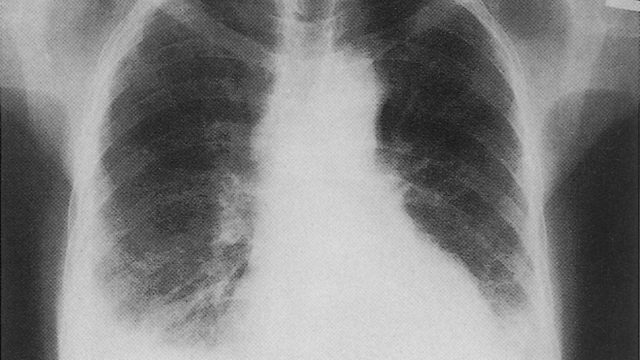

لا يجب التردد حيال استشارة الطبيب المختص عند الإحساس بأي من الأعراض المذكورة للقيام بالفحوصات اللازمة. ويتم عادة العلاج عن طريق سحب المياه من الرئة بواسطة أنبوب بلوري يتم إدخاله عن طريق الفم وهي تقنية غير مؤلمة. وفي حالة أخرى يصف الطبيب أدوية مدرة للبول تفيد في سحب الماء خارج الجسم. (bloom.health)